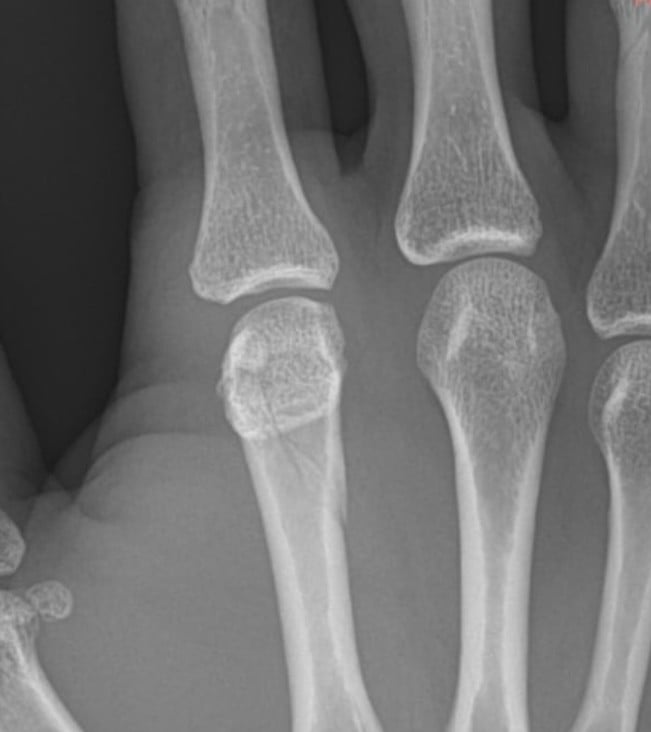

Tras el evento, el propio Bautista dio a conocer detalles sobre su estado físico a través de sus redes sociales, donde compartió una imagen de la radiografía de su mano y confirmó la lesión con un breve mensaje: “Nudillo roto”.